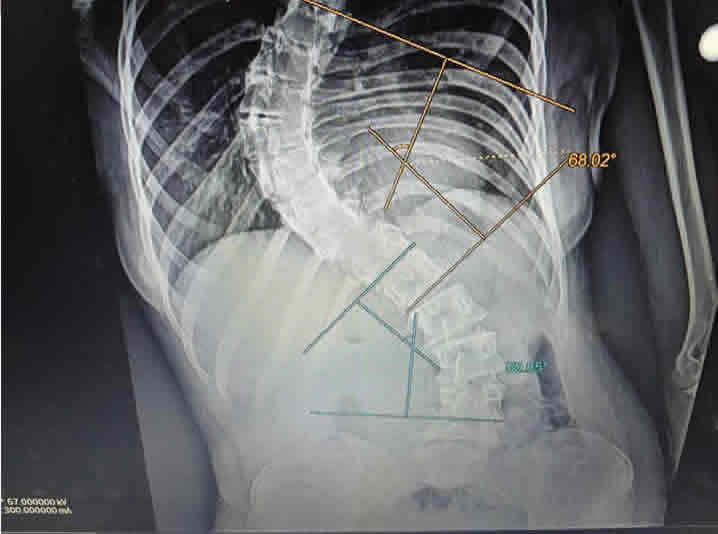

Escoliosis radiografia

Es una deformidad de la Columna Vertebral donde se pierde su alineación normal y se forma una curvatura muy evidente que excede los 10 grados de angulación, se acompaña con desplazamiento lateral y rotación de las vértebras.

El tratamiento conservador mediante el uso de Corsé ortopédico y terapia física está indicado en pacientes que tienen curvas menores de 30 grados, sin embargo, se ha observado que en las curvas mayores, el tratamiento conservador no tiene buenos resultados, por lo que se tendría que valorar el tratamiento quirúrgico para evitar la progresión de la curva.